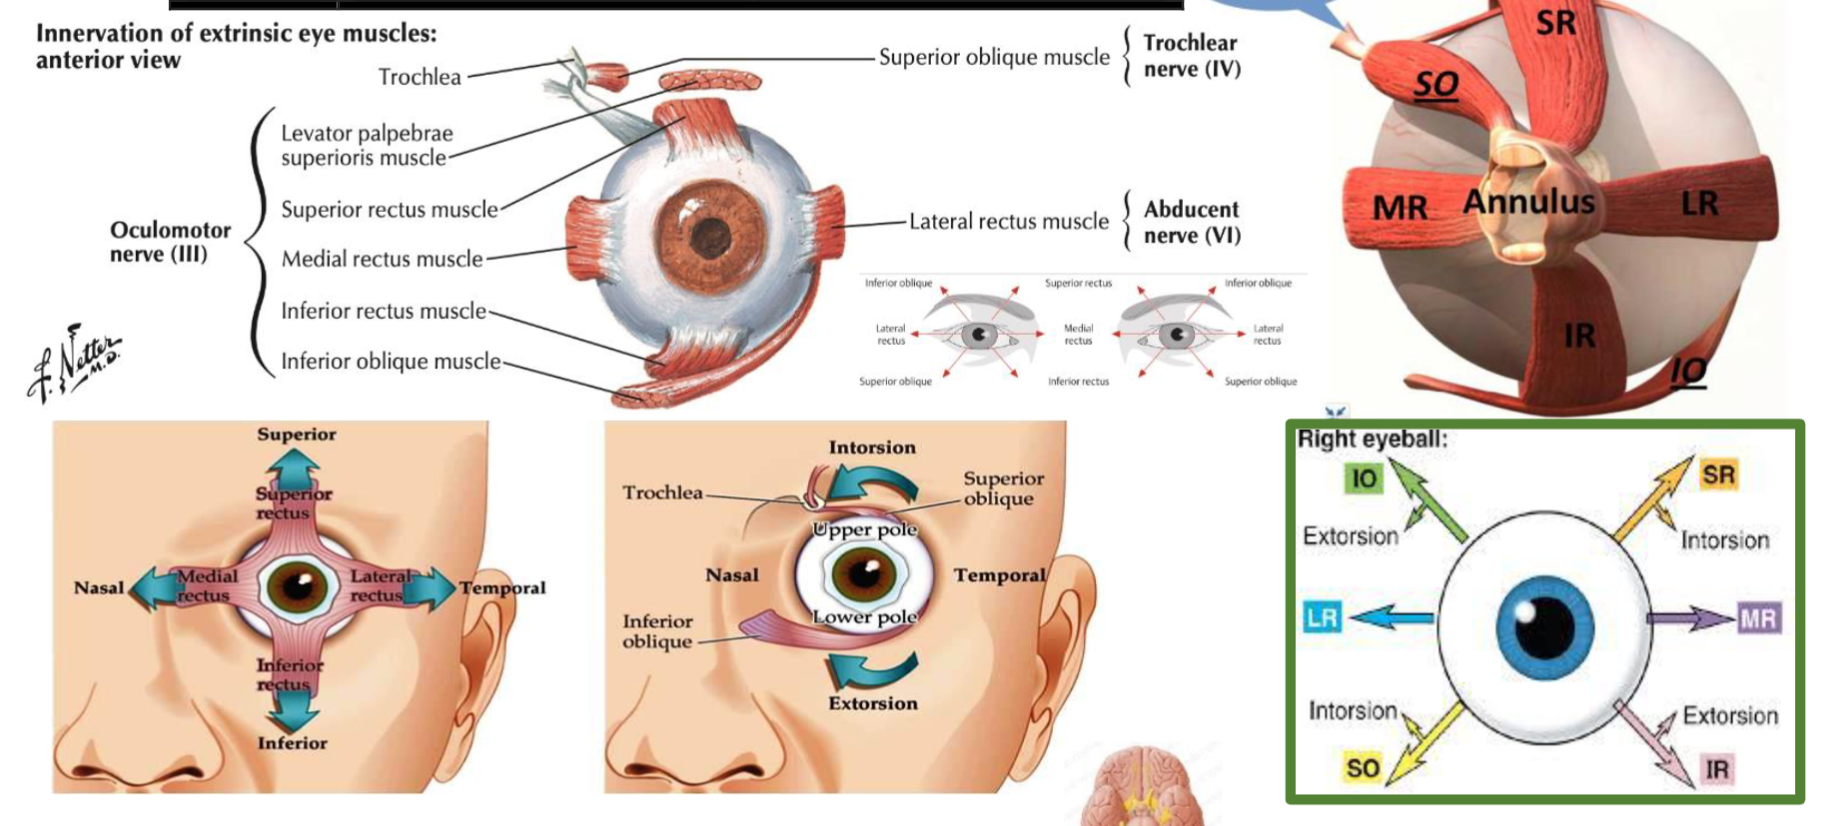

- , 4, 6 Oculomotor, Trochlear, Abducens- CN III, IV, VI; H test

CN III, IV, VI -

Superior orbital fissure Signs: - H test switch fingers at middle - to test otherwise

| Muscle | Innervation | Action |

|---|---|---|

| Superior Rectus | Oculomotor nerve (CN III) | Elevates, adducts, and medially rotates the eyeball |

| Inferior Rectus | Oculomotor nerve (CN III) | Depresses, adducts, and laterally rotates the eyeball |

| Medial Rectus | Oculomotor nerve (CN III) | Adducts the eyeball |

| Lateral Rectus | Abducens nerve (CN VI) | Abducts the eyeball |

| Superior Oblique | Trochlear nerve (CN IV) | Depresses, abducts, and medially rotates the eyeball |

| Inferior Oblique | Oculomotor nerve (CN III) | Elevates, abducts, and laterally rotates the eyeball |

| Levator Palpebrae Superioris | Oculomotor nerve (CN III) | Elevates the upper eyelid |